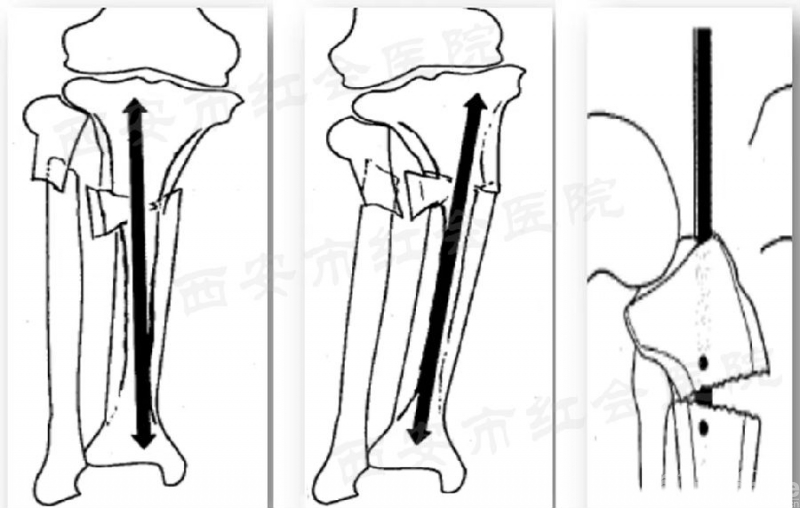

胫骨髓内钉进针点的定位

髓内钉的开口,对应整个手术的成败是至关重要的,因为开口导致手术失败的例子比比皆是。

在冠状面上,进针点偏外会导致内翻畸形,而进针点偏内会外翻畸形;在矢状面上,进针点偏前会导致前凸畸形。

髌外侧入路

仰卧于可透视手术床,铺巾前小腿下垫楔形垫。沿髌骨、髌腱外侧做一长约5cm的弧形切口,切开髌腱外侧支持带,牵开并保护脂肪热,触摸入点,克氏针定位,透视证实,用套筒将髌骨和髌腱往内侧推移,开口,置入导针,随后对骨折进行复位,再按照标准流程植入髓内钉。